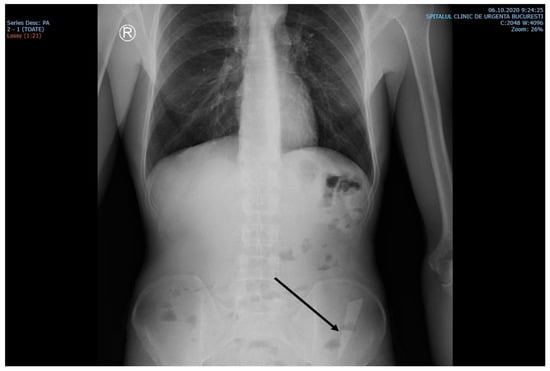

The laboratory examinations of the patient showed leukocytes = 9830/μL, hemoglobin = 12.8 g/dL, platelets = 379,000/μL, ALT = 69 U/L, AST = 48 U/L, PT = 13.6 s, and the rest within normal limits. A chest X-ray at admission showed no acute pleuro-pulmonary lesions. An abdominal X-ray at admission showed discrete aerocolia without radiologically noticeable pneumoperitoneum, hydroaeric levels, and a radiopaque structure in the left flank, denoting a foreign body (Figure 1).

Figure 1. X-ray examination showed an elongated blade (arrow) in the iliac fossa, possibly in the sigmoid colon.